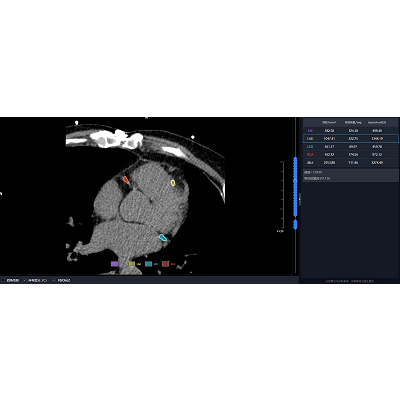

联影智能CT门控钙化积分智能分析系统可自动检出左主干(LM)、左前降支(LAD)、左回旋支(LCX)以及右冠状动脉(RCA)四大主支的钙化病灶并精准标记,智能计算各支血管的钙化积分值和总钙化积分值,支持自定义分支钙化灶编辑,自动生成智能报告,辅助医生对冠状动脉整体钙化程度进行量化评估,助力心血管疾病风险预测。

联影智能CT门控钙化积分智能分析系统能够为心血管疾病风险得评估和诊断提供支持。系统可精准检测并标记冠状动脉的钙化病灶、智能计算钙化积分,通过自动且精准的量化分析,助力医生提升诊断效率,降低漏诊风险。